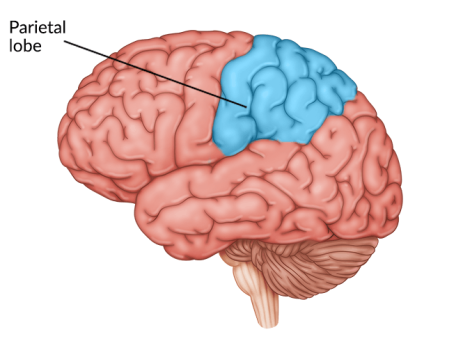

Parietal Lobe Damage: Understanding Symptoms and Treatments

Parietal lobe damage can severely impair a person’s ability to process sensory input. For example, individuals with parietal lobe damage may not recognize sensations such as hot/cold, smooth/rough, etc. Injury to this area of the brain can also create vision deficits and difficulty with spatial awareness. Thankfully, there is hope for improvement through a comprehensive rehabilitation program. In this article we will discuss the major symptoms of parietal lobe damage as well as the treatment process. Understanding Parietal Lobe Damage The parietal lobe rests near the top, middle section of the cerebral cortex, just behind the frontal lobe and above the temporal lobes. Because the brain is divided...